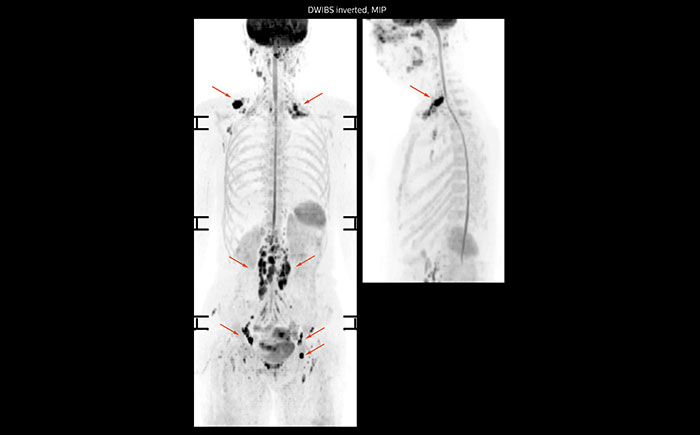

Whole body diffusion

A 61-year-old female with a malignant lymphoma underwent an MRI exam with whole body diffusion weighted imaging (DWIBS) as well as PET. On the images shown, the resolution of DWIBS is better than PET, which allows visualization of the small pelvic lesions and almost no distortion is seen in the neck area.

Prodiva MRI whole body DWI lymphoma, Seirei Mikatahara

Prodiva MRI whole body FDG-PET, Seirei Mikatahara